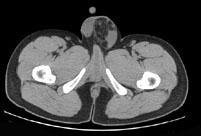

男,29岁,因左腹股沟突发痛性肿物3小时入院,左腹股沟皮下环处有一约4cm×5cm的肿物,触痛甚,质软,基底部有一细蒂,左阴囊发育小,睾丸缺如,CT检查如...

问题 男,29岁,因左腹股沟突发痛性肿物3小时入院,左腹股沟皮下环处有一约4cm×5cm的肿物,触痛甚,质软,基底部有一细蒂,左阴囊发育小,睾丸缺如,CT检查如图所示,下列说法错误的是 ( )

选项 A、腹股沟斜疝 B、左腹股沟区肿块为曲张的精索静脉 C、精索静脉曲张 D、腹股沟直疝 E、左睾丸下降不全

答案 D